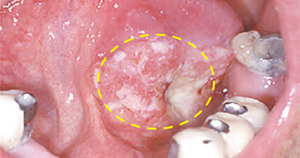

구강암은 입술, 혀, 잇몸, 볼 안쪽, 입천장 등 입안의 어느 부위에서나 발생할 수 있는 암이에요.

구강암은 입안의 점막세포(편평 상피세포)가 비정상적으로 변하면서 생기는 암이에요.

즉, 입안 조직에 생긴 작은 상처나 염증이 제대로 낫지 않고, 세포가 계속 자라면서 종양이 생기는 거죠.

초기에는 단순한 입안 염증이나 구내염으로 착각하기 쉬워요.

하지만 2주 이상 낫지 않거나, 점점 커지는 궤양·혹·붓기가 있다면 구강암을 의심해야 합니다.

- 입안에 하얗거나 붉은 반점이 생기고 잘 낫지 않음

- 혀, 잇몸, 볼 안쪽에 덩어리나 혹이 만져짐

- 시진(눈으로 관찰) : 궤양, 혹, 변색 부위를 직접 확인